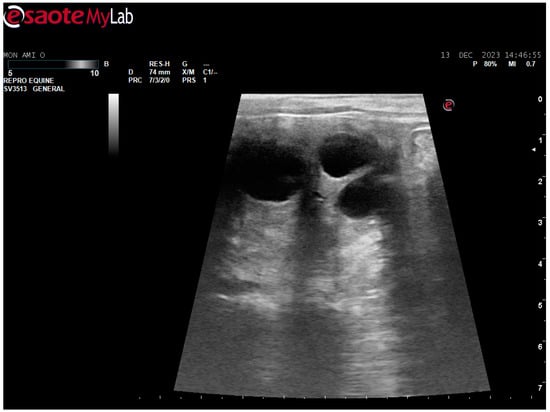

After surgery, the mare’s reproductive system was investigated. Ultrasonographically, slight uterine edema (grade 1 out of 5) and hyperechoic particles (Figure 2), suspected as air in the uterus, were observed. The left ovary was normal in size and echogenicity, present with some 10 to 28.4 mm follicles (Figure 3 and Figure 4). Due to poor perineal conformation, the mare had pneumovagina. Caslic’s vulvoplasty was performed.

Figure 3. Left ovary, present with some >10 mm follicles. Ultrasonographic picture post surgery.

Animals 14 01307 g003

Figure 4. Left ovary, present with 28.4 mm follicle follicles. Ultrasonographic picture post surgery.

Animals 14 01307 g004